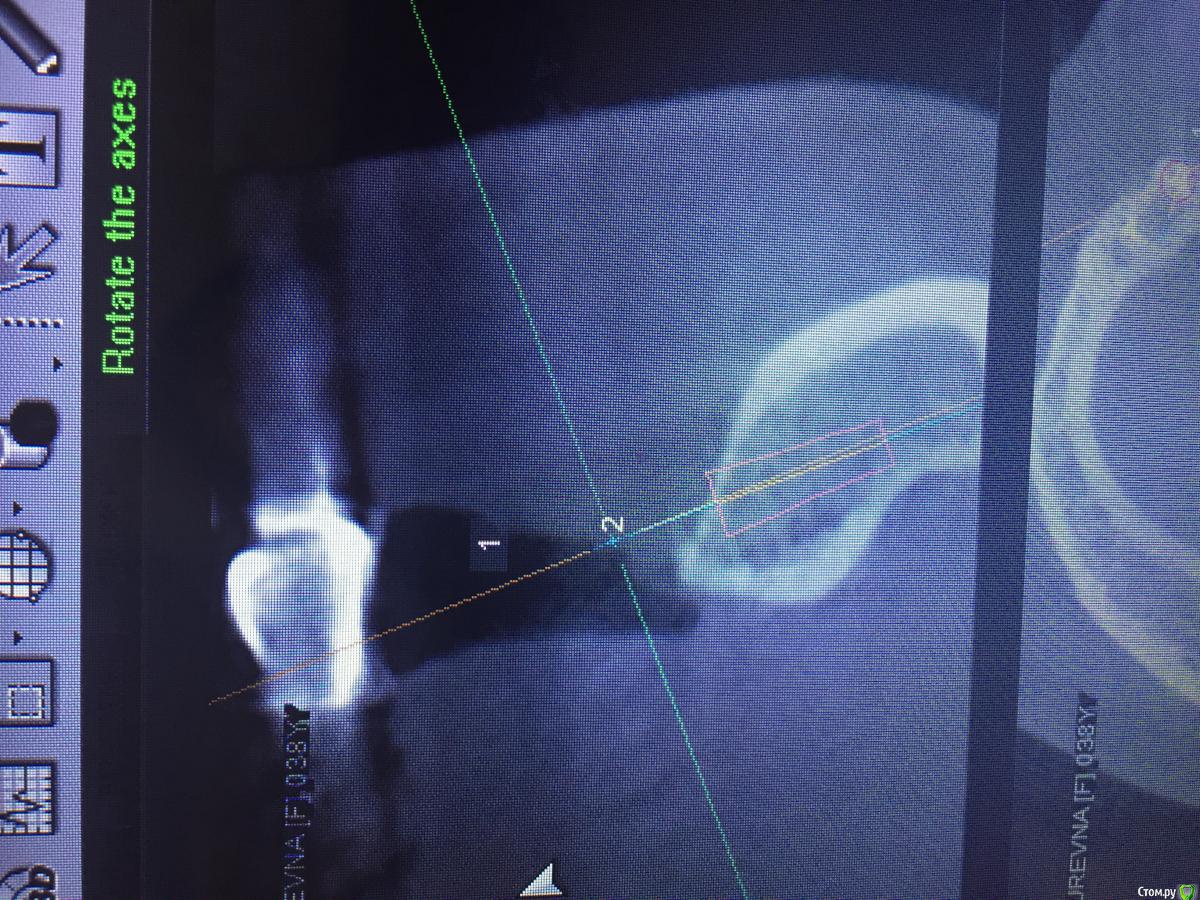

Evikrol Опубликовано 1 мая, 2015 Автор Поделиться Опубликовано 1 мая, 2015 (изменено) Как правильно спозиционировать имплантат? Если есть язычное поднутрение? Это 10, может 8мм? Почему изображение свалилось:-)? Как тут перевернуть:-)) Изменено 1 мая, 2015 пользователем Evikrol Ссылка на комментарий

Evikrol Опубликовано 1 мая, 2015 Автор Поделиться Опубликовано 1 мая, 2015 (изменено) может 8 и не боятся ничего. Да чтож они переворачиваются! Или ауто под надкостницу положить? Изменено 1 мая, 2015 пользователем Evikrol Ссылка на комментарий

faity Опубликовано 1 мая, 2015 Поделиться Опубликовано 1 мая, 2015 область нижней шестерки? по идее 4,5/8 должно хватить, но зачем? ставьте вестибулярнее и 11 войдет на ура до 4,0. Ссылка на комментарий